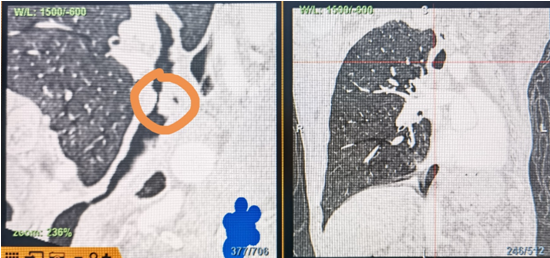

時(shí)間就是生命!了解患者病情后,歐陽海峰立刻啟動(dòng)氣道梗阻緊急救治通道,協(xié)調(diào)院前轉(zhuǎn)運(yùn),急診快速入院流程。凌晨患者入院胸部CT顯示,現(xiàn)存唯一的呼吸通道在右主支氣管處,狹窄處僅約3毫米,患者命懸一線!

運(yùn)用呼吸介入技術(shù),軟硬鏡結(jié)合快速開通氣道,是患者目前唯一可行的治療方案,手術(shù)刻不容緩!但存在麻醉后氣道完全塌陷閉合、大出血、窒息等巨大風(fēng)險(xiǎn)?;颊叽饲敖舆B轉(zhuǎn)診3家醫(yī)院,均建議保守支持治療或轉(zhuǎn)院。歐陽海峰詳細(xì)了解患者病史,全面評(píng)估影像檢查結(jié)果后,決定盡快進(jìn)行手術(shù),組織醫(yī)護(hù)團(tuán)隊(duì)對(duì)患者進(jìn)行持續(xù)密切監(jiān)測(cè),充分保障其術(shù)前安全。